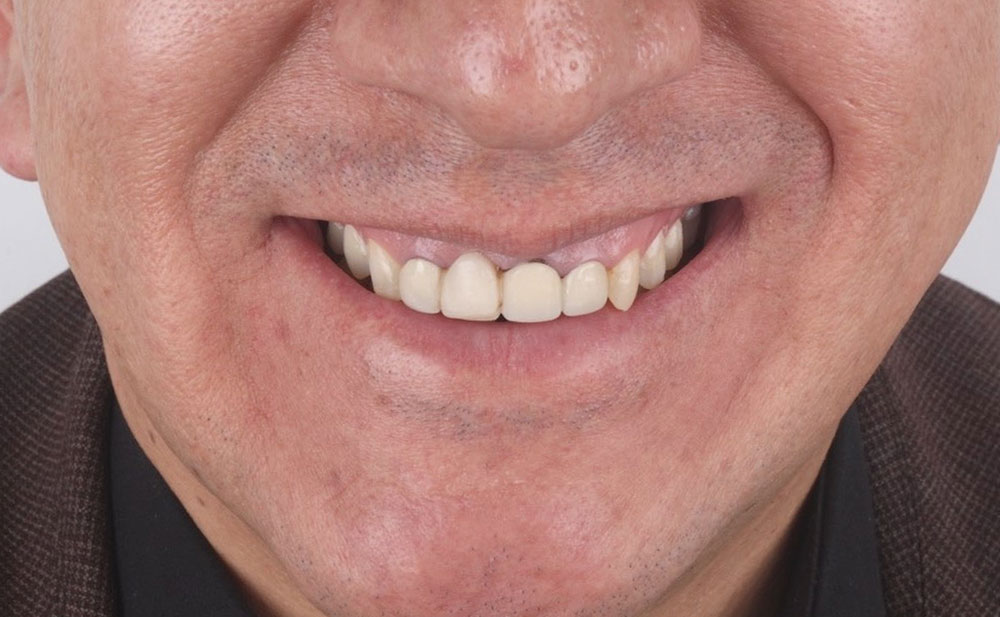

Antes

Antes

Antes

Antes

Antes

Antes

Antes